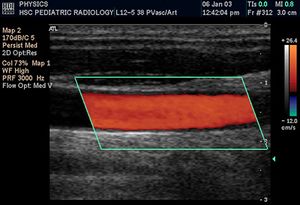

التخطيط الصدى الدوپلري

تكون الصورة عادةً ملونة، فيظهر الدم اما بلون أحمر أوأزرق حسب اتجاه الجريان بالنسبة للمجس الفاحص. ويقدم الجهاز معلومات ممتازة في تقييم صمامات القلب وارتفاع الضغوط الدموية في الأوعية الدموية.